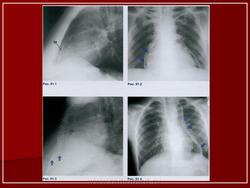

На ЭКГ зубец R значительно расширен (более 0,1 с), резко снижен вольтаж комплекса QRS. При рентгенологическом исследовании характерно отсутствие талии сердца и дифференциации дуг. Контуры сердца выпрямляются, у 25 % больных визуализируется скобкообразная тень обызвествленного перикарда, охватывающая желудочки. Рентгенокимографические зубцы отсутствуют. ЭхоКГ выявляет гипокинезию сердечного контура, увеличение интенсивности эхо-сигналов листков перикарда, снижение диастолического объема сердца и фракции выброса.

Констриктивный перикардит.

Констриктивный перикардит.

Констриктивный перикардит.

Обызвествления перикарда

ID: 8540 Pericardial calcification Dr Frank Gaillard - 10 Feb 2010 Pericardial calcification

ID: 10038 Constrictive pericarditis Dr Paresh K Desai - 13 Jun 2010 Pericardial Calcification on Chest Radiographs.Chest PA and left lateral...